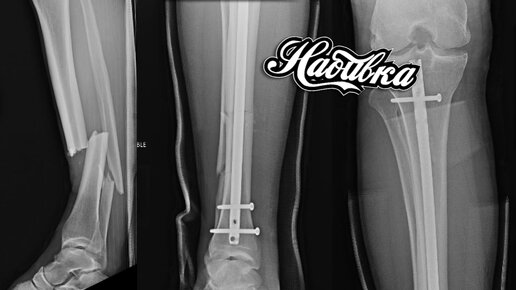

Вокруг единоборств и тайского бокса в том числе существует огромное количество анекдотических ситуаций. Одной из самых любимых мною тем является вопрос набивки конечностей. Сегодня мы поговорим о подготовке голени, так как ошибки в этом могут быть чреваты серьезными травмами. Совет №1. Набивка убивает нервные окончания Те, кто заходили в школу хотя-бы до девятого класса надеюсь поймут, что это полный бред. Давайте представим себе, что нервы на ногах действительно умерли после тяжелых тренировок...